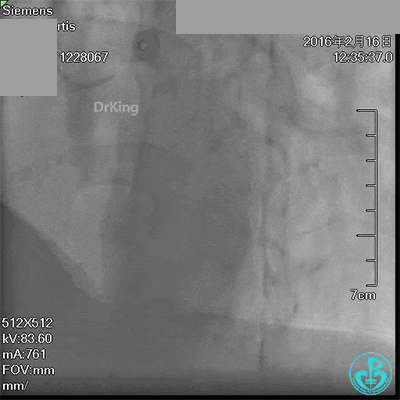

急诊冠脉造影发现粗大前降支近端严重狭窄,行PCI处理,支架膨胀良好,血流3级。

急诊术中导丝在锁骨下通过困难,曾在局部推注造影剂造影,回顾造影结果发现局部小血管破裂造影剂渗漏。